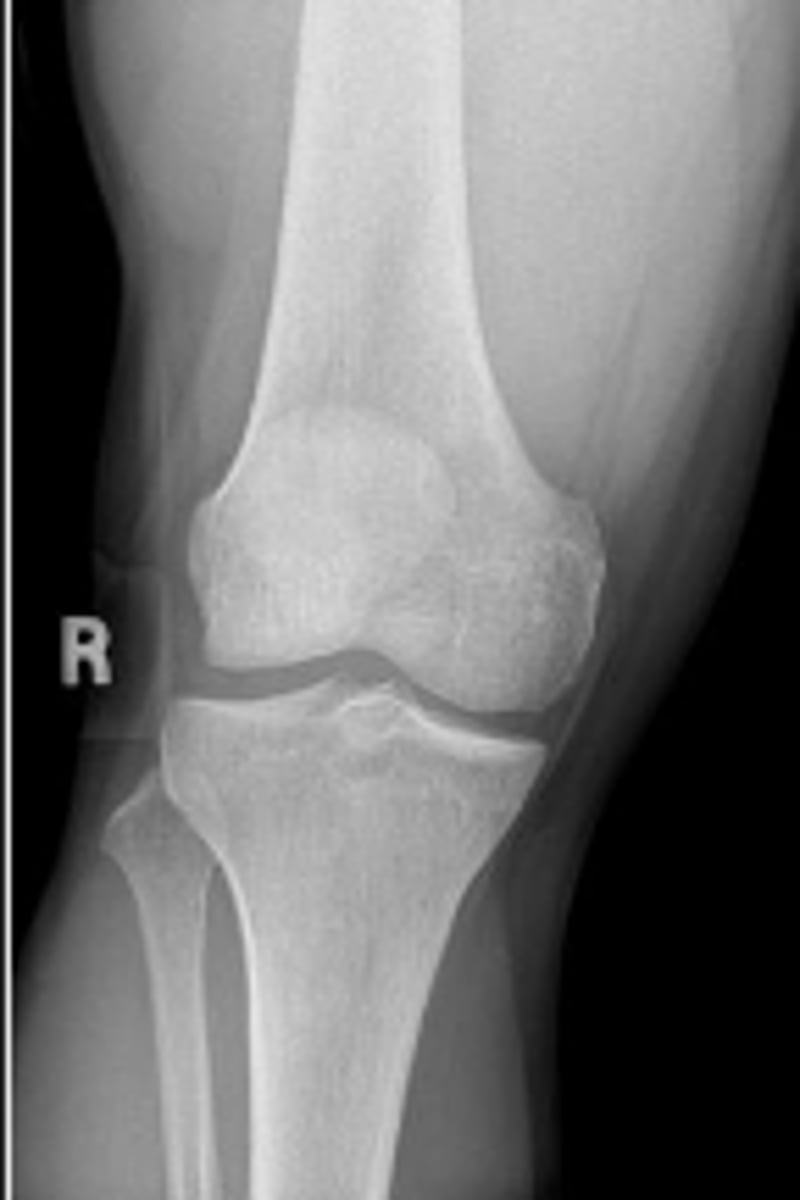

Right AP knee

What is the name of the radiographic view?

Lateral tibial spine/eminence

What is outlined?

Medial tibial spine/eminence

Lateral tibial plateau of the right knee

Lateral tibial condyle of the right knee

The right medial & tibial plateaus and the right

medial and lateral condyles right knee